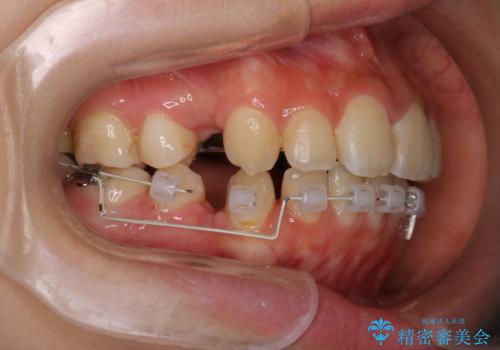

【ハーフリンガル】口元を下げたい!

- ハーフリンガル

- 口元が出ていることを主訴に来院されました。

歯を抜いてスペースを作ることで、前歯を下げることができました。

ハーフリンガルということで治療期間が3年近くかかりましたが、口元もしっかり下がり満足していただきました。